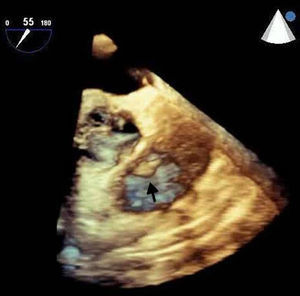

A 42-year-old man with a history of hypertension, type 2 diabetes mellitus and obesity was referred to our center due to the incidental finding of a mass adjacent to the pulmonary valve on a routine transthoracic echocardiogram (Figure 1). He was asymptomatic and physical examination and laboratory values were unremarkable. The transesophageal echocardiogram (Figure 2) revealed a pedunculated, highly mobile hyperechogenic mass, measuring 8 mm × 7 mm, attached to the right pulmonary valve leaflet. The pulmonary valve was functionally normal, with no observed pulmonary regurgitation or stenosis, and no masses were visualized on any other valves or heart chambers. Computed tomography angiography excluded significant coronary stenosis and confirmed the presence of a mass at the level of the pulmonary valve (Figure 3). We concluded that it most likely represented a papillary fibroelastoma. Surgical excision of the mass was decided upon due to its mobility and location, resulting in high risk for embolization. It was successfully resected, with preservation of the valve apparatus. Histopathological examination confirmed the diagnosis of papillary fibroelastoma (Figure 4).